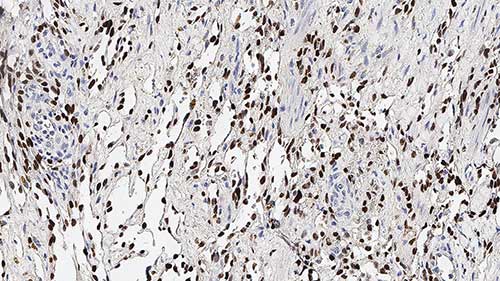

Human skin, Kaposi's sarcoma: immunohistochemical staining for HHV8. Note nuclear staining of neoplastic spindle cells. Human Herpesvirus 8: clone 13B10

Human herpesvirus type 8 (HHV8), is the proposed etiological agent of Kaposi's sarcoma (KS). It is reported that HHV8 has been demonstrated in KS tissues by immunohistochemistry, in situ PCR and also in situ hybridization. HHV8 encodes a latent nuclear antigen (LNA) which is the product of the viral gene ORF73. LNA is capable of forming a complex with retinoblastoma susceptibility gene product which may be related to its oncogenic activity. HHV8 has been reported to be expressed in multicentric Castleman's disease (MCD) and in angioimmunoblastic lymphadenopathies. The localization of HHV8 in subcapsular spindle cell proliferations, which is where early intranodal KS begins, and endothelial cells in Castleman's disease may explain the link between intranodal KS and MCD. In MCD, HHV8 is reported to be expressed in mantle zone large immunoblastic B cells.

Human Herpesvirus 8 (HHV8) is recommended for the detection of specific antigens of interest in normal and neoplastic tissues, as an adjunct to conventional histopathology using non-immunologic histochemical stains.